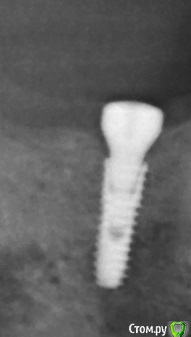

Dark Destroyer Опубликовано 7 ноября, 2016 Поделиться Опубликовано 7 ноября, 2016 Уважаемые форумчане,подскажите пожалуйста,это формирователи от Osstem стоят на имплантатах? Ссылка на комментарий

red_butler Опубликовано 7 ноября, 2016 Поделиться Опубликовано 7 ноября, 2016 +1 к дентиуму, покажите фото. Я бы перекрутил, на rg, формики перекошенные. Ссылка на комментарий

Nazim_NV86 Опубликовано 7 ноября, 2016 Поделиться Опубликовано 7 ноября, 2016 Почему вы решили что они не осстем?Сфотографировали бы торцевую часть, я бы вам точно сказал.На осстемах последних 2-3 лет там должно быть написано (судя по размерам) 5 H5. Ссылка на комментарий

dok1 Опубликовано 8 ноября, 2016 Поделиться Опубликовано 8 ноября, 2016 На DIO похожи. Ссылка на комментарий